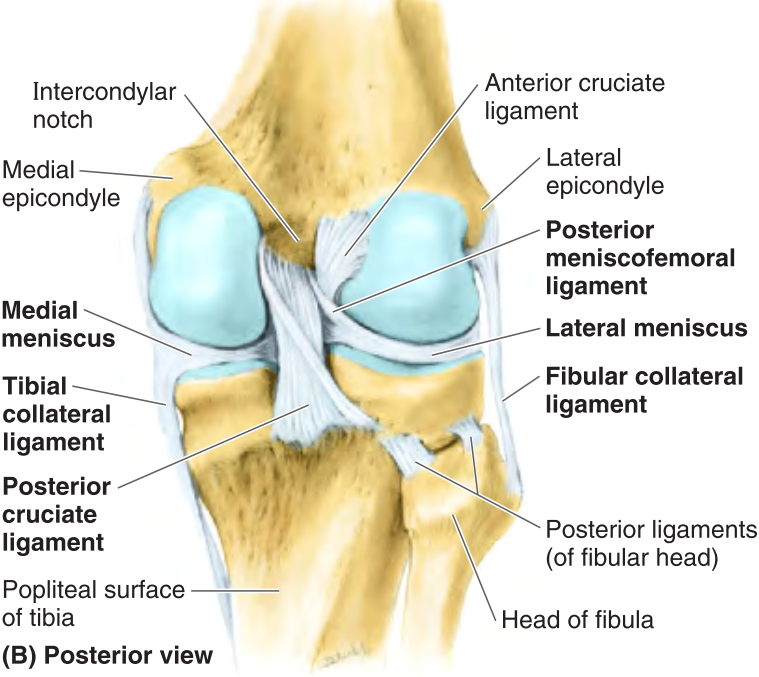

Describe the minisci of the knee joint.

There are two, the lateral and medial menisci. They are incomplete rings of dense connective tissue paritally covering the articular surface of the tibial condyles.

The most stable position of the knee joint is when it is in the erect, extended position where contact of the articular surfaces is maximized and the primary ligaments of the knee are taut.

What is the purpose of the lateral collateral ligament?

The lateral (fibular) collateral ligament (LCL) attaches the lateral epicondyle of the femur to the fibular head.